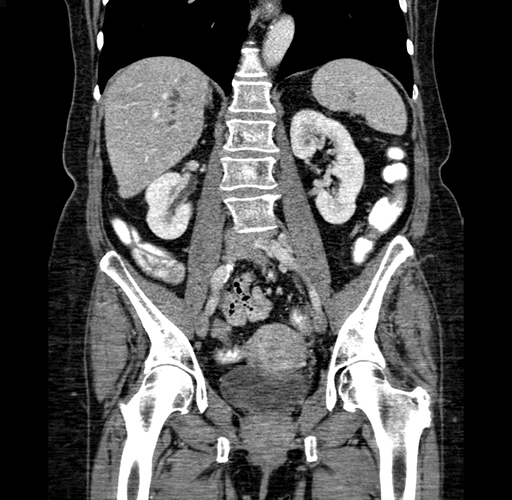

Pre-Chemo: Axial Venous

Imaging analysis

Based on your CT findings, which issue(s) would give reason for "planned slowing down moment(s)" in this case?